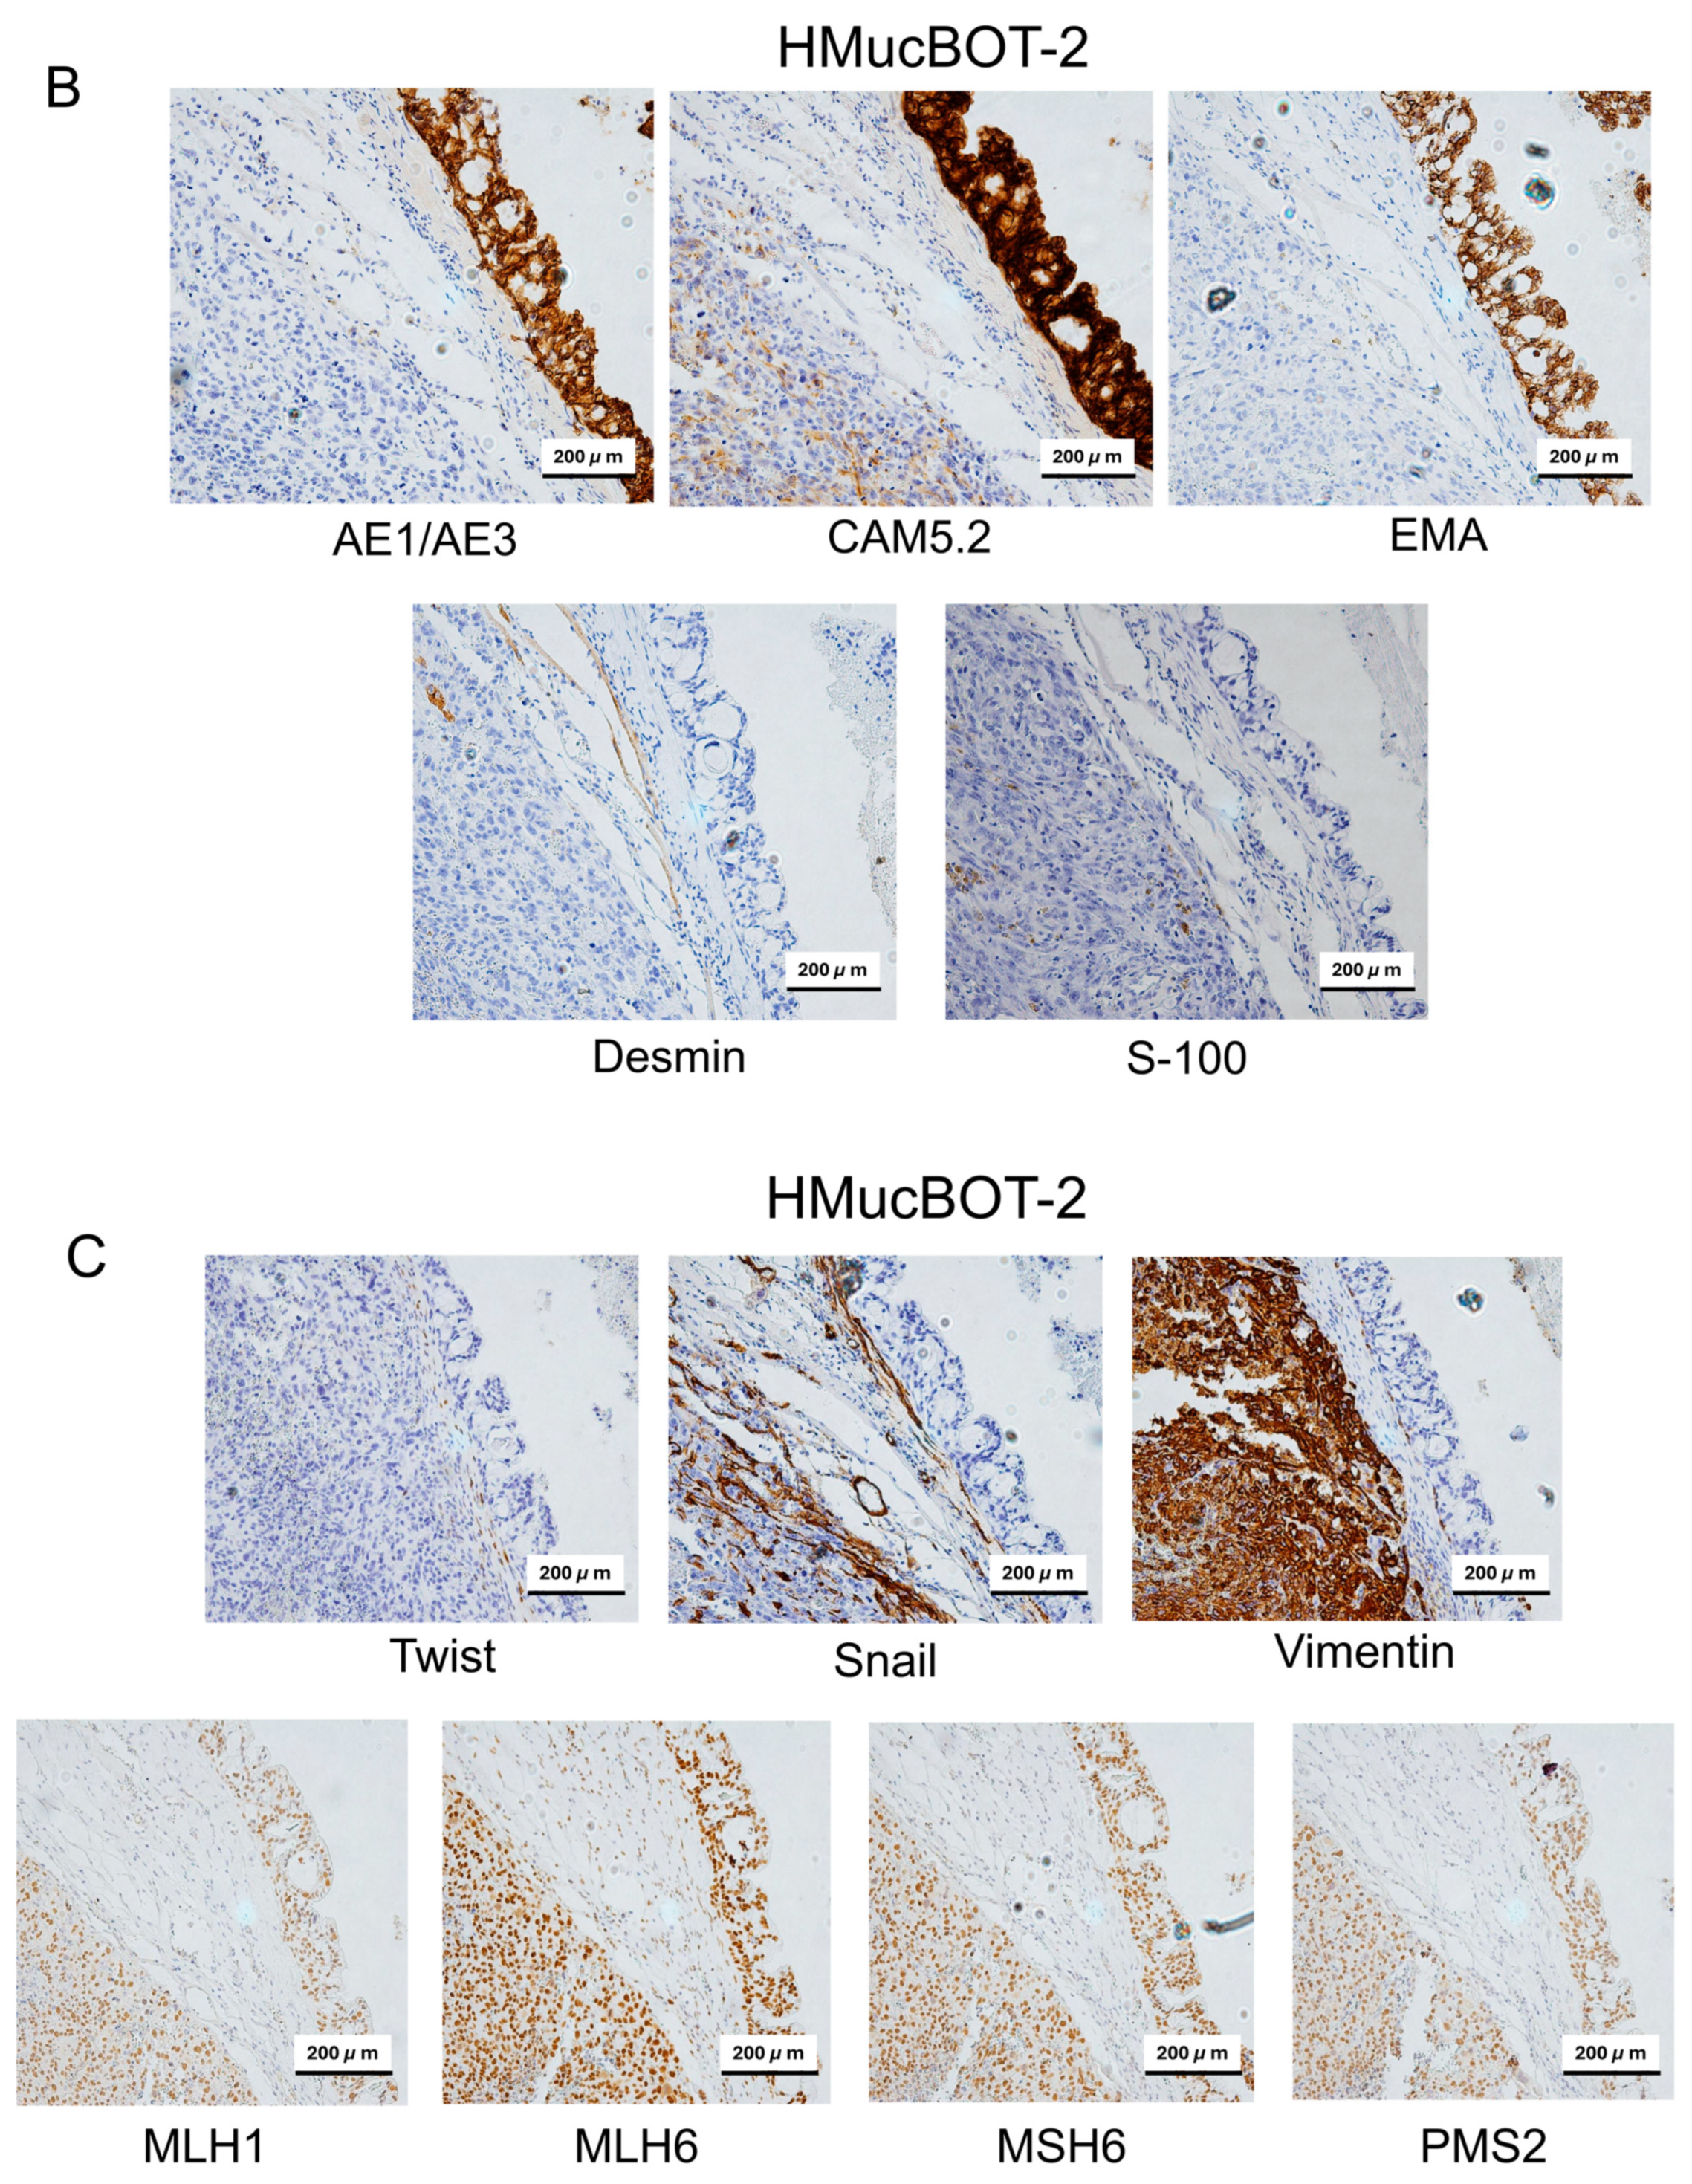

3.6. Characterization of Mouse Xenograft Tumors